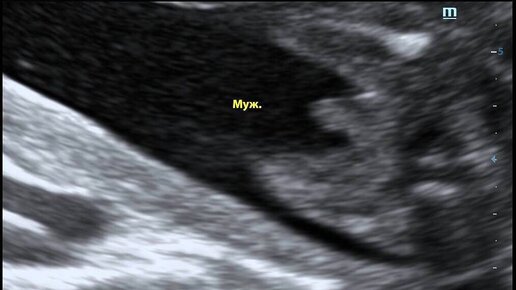

В эфире рубрика "УЗИ_Витроклиник". Лайк интересным снимкам. Во втором триместре будущие родители могут узнать пол ребенка. На этом фото мы видим половые органы мальчика. На сроке 20 недель врач проводит второе плановое УЗИ. С его помощью он оценивает соответствие степени развития плода его сроку, размеры его тела, головы, состояние внутренних органов и крупных сосудов, основные структуры головного мозга, измеряет частоту сердцебиения ребенка. Начиная с 15 недели внутриутробного развития можно определить пол ребенка...